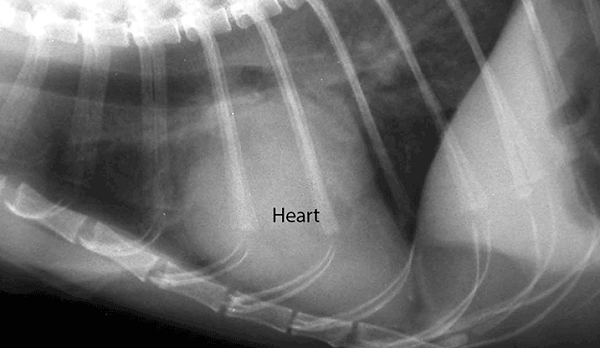

Bác sĩ thú y có thể nghi ngờ mèo bị suy tim sung huyết nếu khám sức khỏe cho thấy sự thay đổi màu mô nướu, rối loạn tĩnh mạch, nhịp tim không đều, huyết áp cao và / hoặc tiếng tim không đều. Nếu phát hiện thấy bất thường, việc xét nghiệm máu, chụp X quang, điện tâm đồ và / hoặc siêu âm tim thường được khuyến nghị để chẩn đoán suy tim sung huyết ở mèo. Bác sĩ thú y cũng có thể giới thiệu mèo con của bạn đến bác sĩ tim mạch nếu họ nghi ngờ nó đang bị suy tim sung huyết.